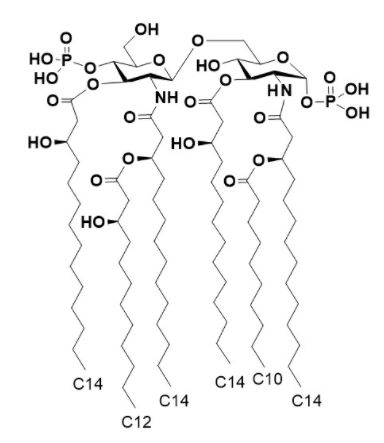

合成アルカリゲネス菌リピドAの優れたアジュバント活性を証明

ヒトやマウスの腸管関連リンパ組織の内部に共生し、免疫活性化を行うアルカリゲネス菌の菌体成分であるリピドAの化学合成法を確...